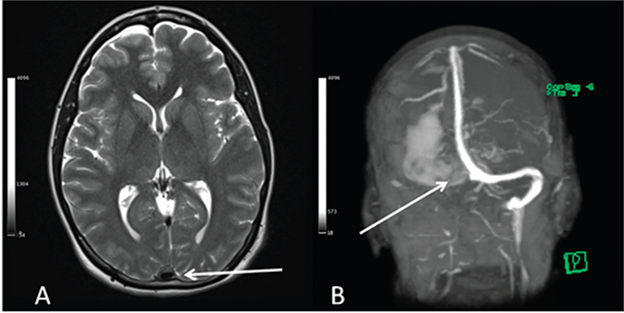

Chìa khoá cho chẩn đoán đó là triệu chứng lâm sàng và dấu khiếm khuyết thần kinh khu trú do CVT tiến triển tăng dần từ từ chứ không tối đa khi bắt đầu như đột quỵ động mạch, MRI não có tiêm thuốc cản từ sẽ cung cấp thông tin chi tiết cho nhu mô não và hổ trợ tốt cho việc chẩn đoán

Hình 2: Chụp cộng hưởng từ cho thấy huyết khối ở hội lưu xoang (mũi tên trắng ở A) và ở xoang ngang (mũi tên trắng ở B).